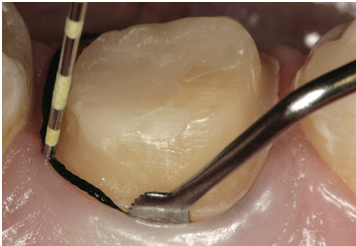

Fig 4. A V-shaped sulcus with a 0.2-mm width is required for access for the wash or syringe material.

Figure 4

Tissue Management

Tissue management is another key step in the fixed prosthodontic landscape. Gingival retraction cords remain the most commonly practiced procedure for tissue management. The goal is to achieve a V-shaped sulcus at a 0.2-mm minimum width, whether a single cord or double cord technique is used. The V-shaped sulcus with a 0.2-mm width creates access for the wash or syringe material so that enough volume may be placed into the desired area and removed in one piece without tearing (Figure 4).